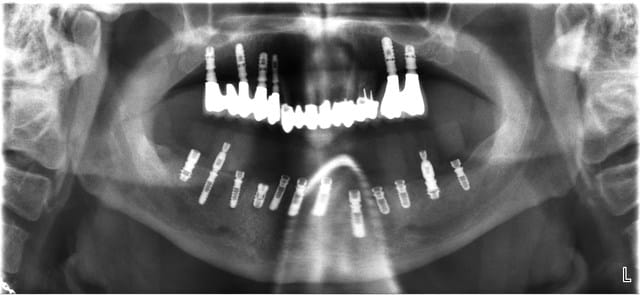

Voici 2 clichés radiologiques qui peuvent paraître surprenants (ici c'est un implant easyimplant à connexion type astra), le premier en juillet 2009 le jour de la pose de la couronne et le deuxième ce mois d'août 2011 (certes vous êtes obligé de me croire, mais ce n'est pas la première fois que j'observe ce phénomène). Ici, le patient procède à un contrôle de plaque parfait.

> Voici 2 clichés radiologiques qui peuvent paraître surprenants (ici c'est un

> implant easyimplant à connexion type astra), le premier en juillet 2009 le jour

> de la pose de la couronne et le deuxième ce mois d'août 2011 (certes vous êtes

> obligé de me croire, mais ce n'est pas la première fois que j'observe ce

> phénomène). Ici, le patient procède à un contrôle de plaque parfait.

Et bien moi je te crois tout à fait: l'os a tendance à croitre du fait de la stimulation et cela nous est caché (presque toujours) par l'agression bactérienne chronique, c'est ce que je crois.

growly vraiment super tes 2 radios

en voila 1 sinus lift avec des leones mais il était facile sur le dernier j'ai utilisé un cap de 1,5 enfoui, on verra la réponse osseuse